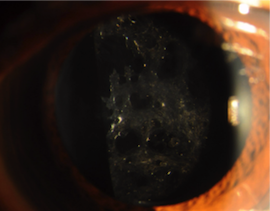

過熟白内障

皮質は全体に白くなり、膨らんで、緑内障の発作を起こすことがあります。このような場合は、放っておくと失明の危険があるので、すぐに白内障手術をしないといけません